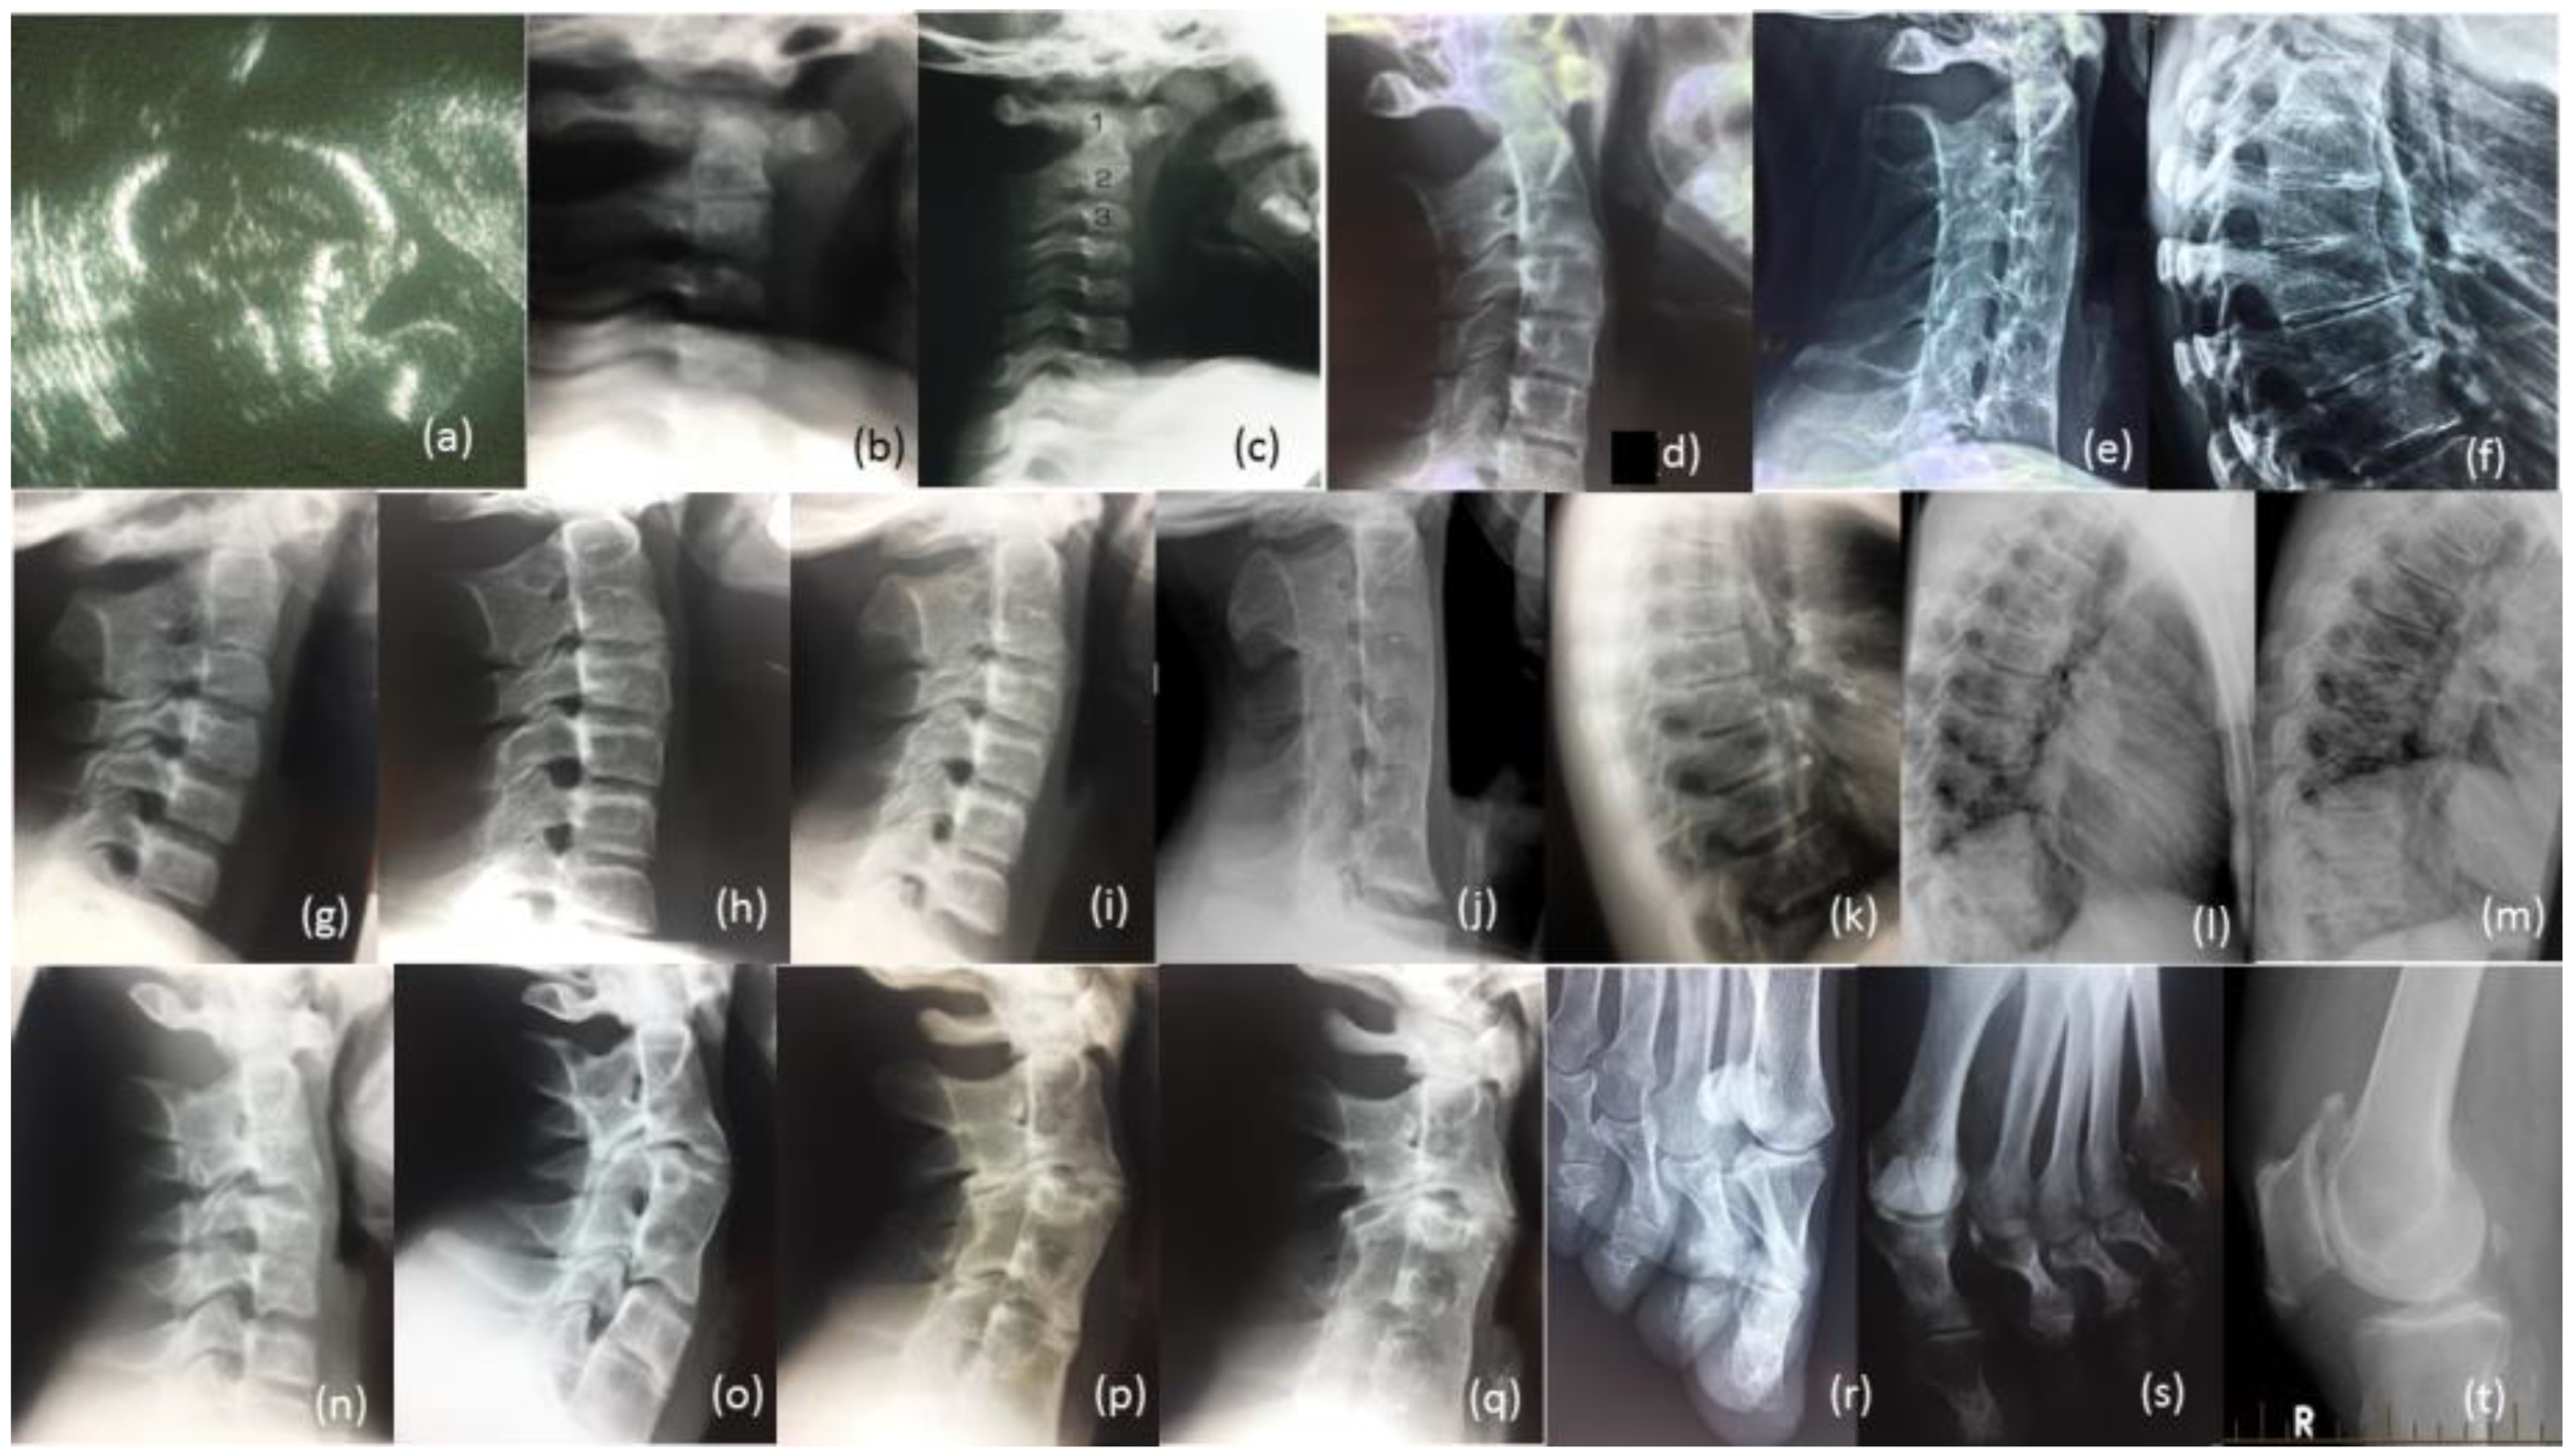

3.1.4. Male Cousin (IV-5)

3.1.5. Familial Skeletal Anomalies

| Cousin (IV-5) | M | 17–50 | Carpal Tarsal Coalition, Pisiform not tested No hearing impairment, Progressive vertebral fusion, Severe speech impairment, short tongue and microstomia. |